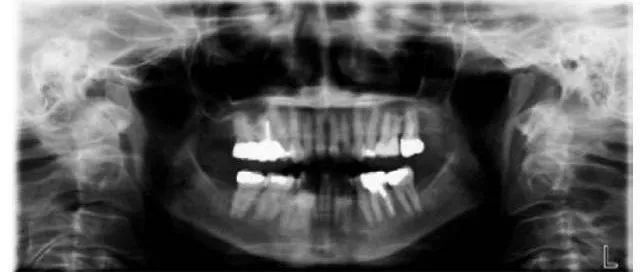

全景片就是可以在一张胶片上可以完整、清晰地显示上颌骨、下颌骨全貌,上下颌牙列情况,牙槽骨情况,能清晰显示上颌窦腔、窦壁、窦底情况,以及颞颌关节情况,并对颌骨周围疾病的诊断提供帮助。

因为全景片可以精确测定牙齿倾斜角度、牙周软组织情况、牙根情况、牙槽骨质情况,解剖形态的精确测量为医生术前的诊断分析与设计提供全景样图像依据,口腔医生借此能更好地为患者设计治疗方案。

拍摄全景片是口腔治疗之前很重要的一个检查过程,医生通过全景片可以观察到牙齿的健康状况,是否有隐形龋齿、埋伏阻生牙、多生牙、牙槽骨吸收、牙龈萎缩、口腔内是否长有瘤体等。在做牙齿种植、牙齿矫正、牙齿修复、智齿拔除等之前,均需要拍摄口腔全景片。